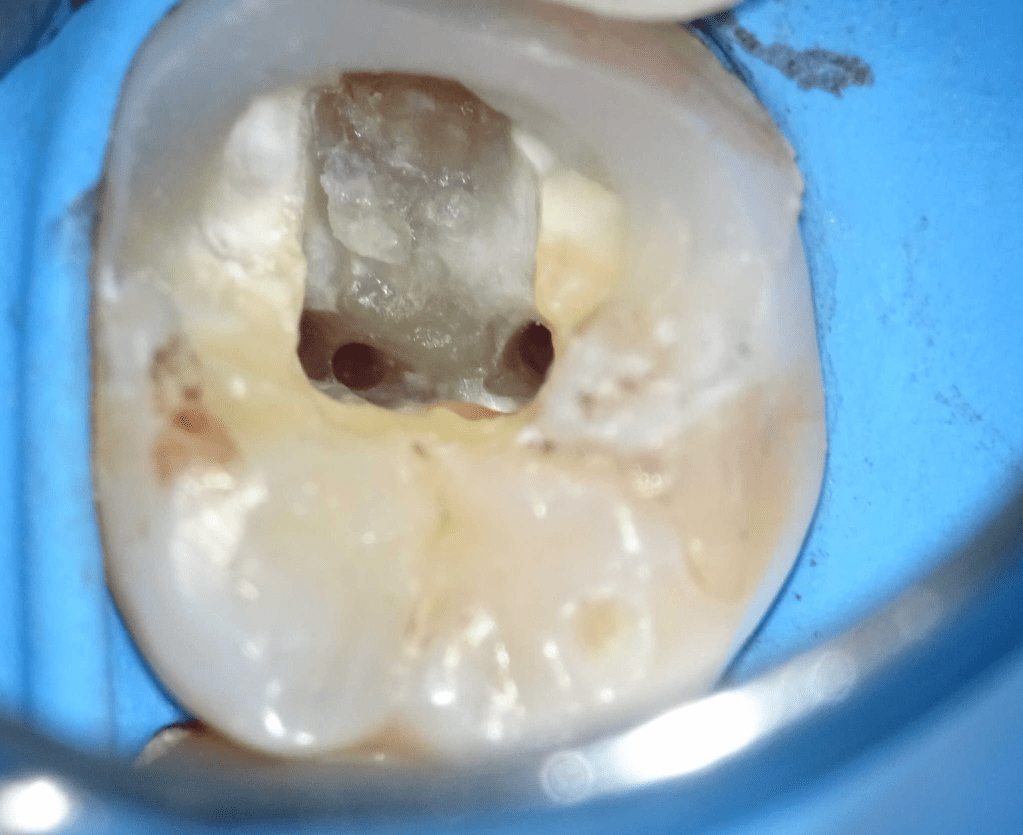

Pulpotomía biodentine + reco preendio